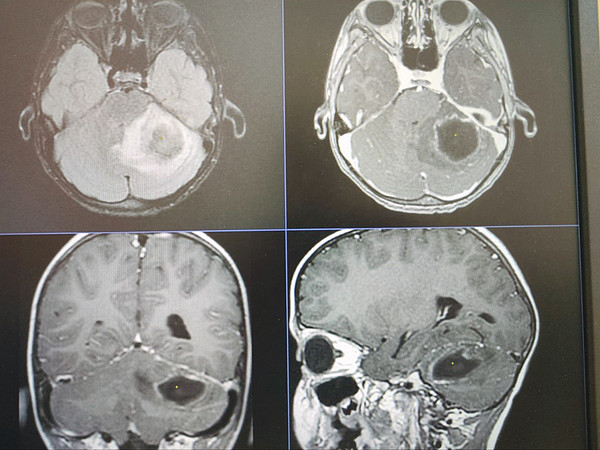

< < <IMG_20240806_161258_775IMG_20240806_161302_196IMG_20240806_161302_226IMG_20240806_161312IMG_20240806_161333

IMG_20240806_161333.